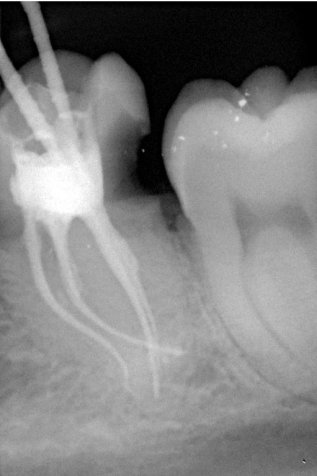

Da die Wurzelkanäle sehr klein sind und sich oft verzweigen, ist es nicht immer einfach, alle Kanäle mit ihren Seitenästen aufzufinden.

Bei der modernen endodontischen Behandlung können durch ein Dentalmikroskop auch kleinere Kanälchen aufbereitet werden, die man auch mit einer Lupenbrille nicht finden würde.

Nur wenn das Wurzelkanalsystem komplett aufgefunden und gereinigt wird, hat eine Wurzelkanalfüllung eine gute Langzeitprognose.

Fallbeispiel für einen komplexen Kanalverlauf